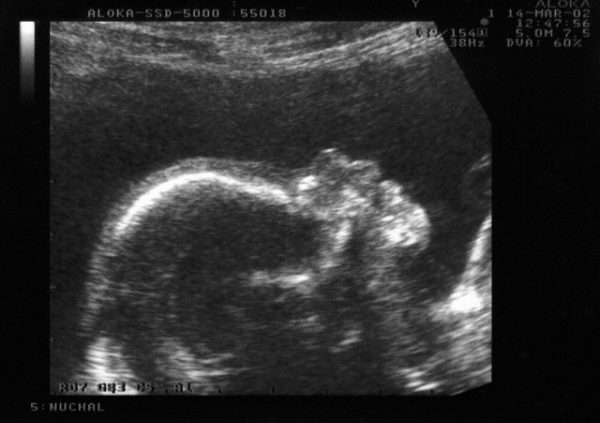

L’ecografia morfologica è uno screening ecografico importante consigliato a tutte le gravide nel II trimestre della gestazione daeseguire tra la 19ma e la 21ma settimana. In tale periodo il feto è sufficientemente grande per permettere di valutare la regolare morfologia e la funzione degli organi. Vengono sistematicamente esaminati la testa, la conformazione dello scheletro (teca cranica, colonna vertebrale, cassa toracica, bacino ed arti) e gli organi (encefalo, polmoni, cuore, intestino, stomaco, reni, parete addominale, cordone ombelicale, genitali) ecc..